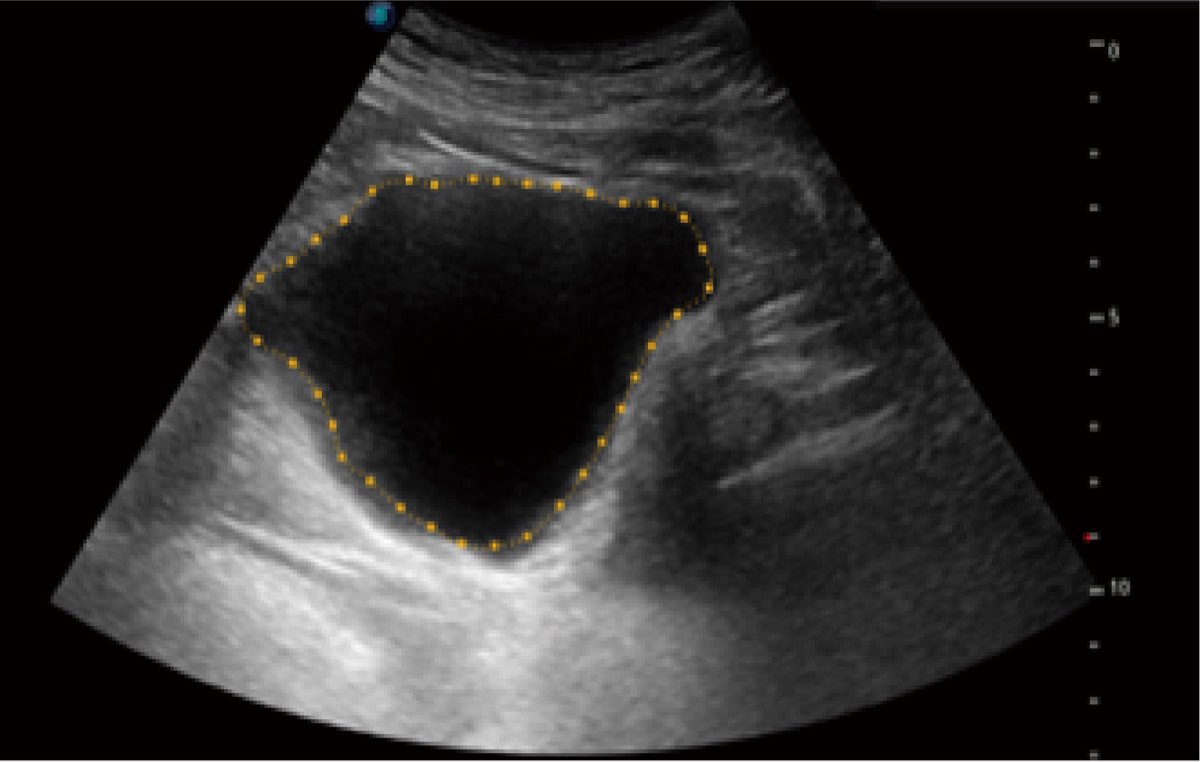

Przy pracach nad aparatem ProPet 60 uwzględniono najważniejsze preferencje i potrzeby weterynarzy, oferując finalnie przystępne cenowo i odpowiednio wyważone połączenie znakomitej precyzji klinicznej, zwiększonej wydajności i przemyślanego przebiegu pracy, niezastąpione w codziennej praktyce weterynaryjnej. Dzięki dostępowi do pełnej gamy głowic HD rozwiązanie to spełnia wszystkie potrzeby w zakresie obrazowania, umożliwiając wykonywanie badań jamy brzusznej, małych narządów, ortopedycznych, badań podczas rozrodu, a nawet badań serca i klatki piersiowej, a to wszystko przy doskonałym stosunku jakości do ceny.